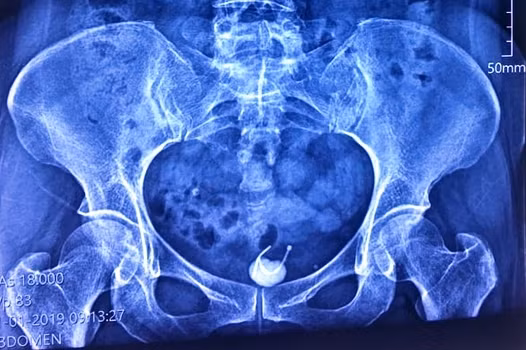

Bệnh nhân là bà T.T.H, 54 tuổi, ngụ Đồng Nai nhập viện trong tình trạng đau bụng vùng hạ vị kèm tiểu khó. Qua thăm khám kết hợp với kết quả siêu âm, bác sĩ phát hiện bệnh nhân có dị vật hình chữ T qua thành bàng quang và có sỏi bàng quang.

| Ảnh chụp X-quang cho thấy vòng tránh thai bị mắc kẹt ở bàng quang người phụ nữ. Ảnh: BSCC |

Bác sĩ Phan Văn Ở, Phó Giám đốc bệnh viện cho biết, dị vật là chiếc vòng tránh thai hình chữ T. Chiếc vòng này theo như bệnh nhân kể thì đã được đặt từ 31 năm trước, song đã bị rơi khỏi vị trí cố định ban đầu, chiếc vòng đi xuyên thành bàng quang và tạo sỏi đã làm chị H. đau bụng và tiểu khó.

Bác sĩ Phan Văn Ở nhận định thêm, trường hợp vòng tránh thai mắc kẹt ở bàng quang là hi hữu, bình thường vòng tránh thai nếu đi lạc sẽ rơi vào ổ bụng.